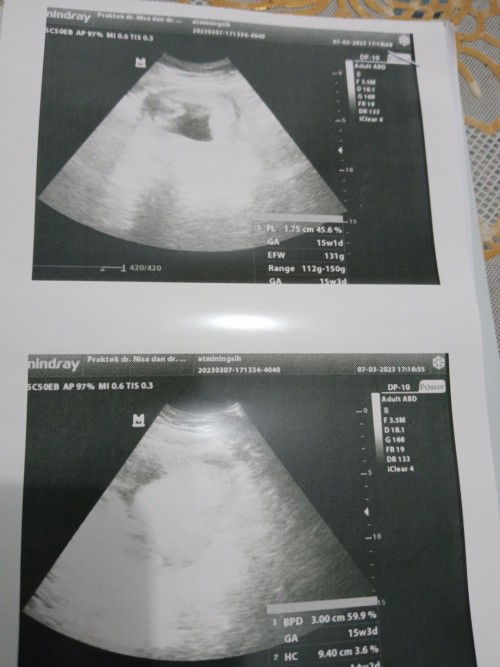

Halo bunda td sore saya kan USG, nah kebetulan usia kandungan 15w2d,pas diusg saya tanya detak jantung normal gk dok,dijawab normal tp tidak bisa denger djj kalo mau denger pake dopler ke bidan,emang alat USG GK bisa denger djj ya Bun?? Terus saya bilang sering pusing sakit kepala kaya migren minta tambah darah tp gk dikasih dengan alasan saya sudah konsumsi folamil Genio yg mana kandungan di dalam sudah lengkap.#bantusharing